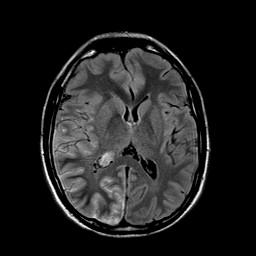

Rationale: Epilepsy is a cause of major morbidity in Sturge Weber syndrome, a segmental vascular neurocutaneous disorder classically associated with facial angiomas, glaucoma, and leptomeningeal capillary-venous type vascular malformations. Seizures occur in more than 75% of affected individuals and are a challenge to treat. The phenomenon of prolonged ictal paresis is a rare seizure sign that can be due to lesions affecting the centro-parietal lobe. Use of steroids to treat leptomeningeal inflammation resulting from angiomatosis of Sturge Weber syndrome has not been reported. Methods: Case Report : A case of a patient with Sturge Weber syndrome presenting with partial seizure like episodes with prolonged post-ictal paralysis, extensive leptomeningeal T2 hyperintensity noted on MRI with good response to Dexamethasone Results: A 24 year male was brought to our hospital after developing persistent left hemiparesis. He had been having brief spells of right sided headache and left hemiparesis for the past 18 months and was on Oxcabazepine for presumed seizure with post-ictal paralysis. He reported recent subtle twitching of the left face and eyes, left hemiparesis and psychomotor slowing with right frontal-temporal headaches but deficits were not resolving like prior episodes. His initial examination showed dysarthria, left homonymous hemianopia, left sided facial weakness, left hemiparesis and left hemianesthesia and although no clinical seizures were noted at this time, Valproic Acid was added for suspected partial status epilepticus and post-ictal paralysis. A 24 hour cEEG showed diffuse right hemispheric slowing, but no ictal activity. MRI brain with contrast showed extensive leptomeningeal FLAIR hyperintensity and enhancement throughout the right cerebral hemisphere consistent with leptomeningeal angiomatosis as well as prominent venous flow voids. Cerebral angiogram showed absence of right hemispheric cortical veins and aberrant venous outflow through multiple pathways, but no AVM or dural AV fistula. After 9 days of persistent deficits, he was started on Dexamethasone 4 mg every 6 hours, which was tapered to 2 mg Q6H with significant improvement in his headaches, left arm strength and communication skills within the next 3 days, and he was discharged with a tapering regimen over 10 days. MRI brain 5 weeks later showed interval decrease in size of previously noted dilated flow voids within the right parietal lobe and collateral draining veins. There was near complete resolution of previously noted leptomeningeal FLAIR hyperintensity. Follow up neurological examination 6 weeks post-discharge showed complete resolution of his neurologic deficits and spells. Conclusions: We report a case of persistent left hemiparesis in a patient with Sturge Weber syndrome attributed to leptomeningeal inflammation of the right cortical hemisphere which showed interval improvement of radiological findings and resolution of neurological deficits with Dexamethasone treatment. Conclusions: We report a case of persistent left hemiparesis in a patient with Sturge Weber syndrome attributed to leptomeningeal inflammation of the right cortical hemisphere which showed interval improvement of radiological findings and resolution of neurological deficits with Dexamethasone treatment. Funding: No funding was received in support of this abstract.